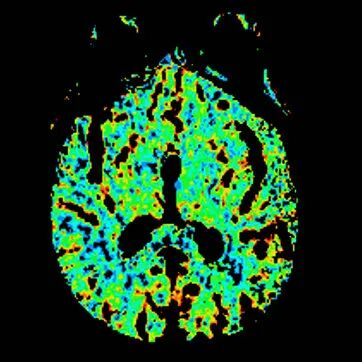

多模态CT。

查体BP 160/89mmHg,清醒,双眼左侧凝视位、不可纠正,混合性失语,右侧中枢性面舌瘫,右侧肢体肌力0级,右侧病理征阳性。NIHSS评分18分。随机血糖4.8mmol/L。心电图:正常。颅脑CT无出血及新发梗死灶,多模态CT示左侧大脑中动脉闭塞、左侧大脑半球低灌注。